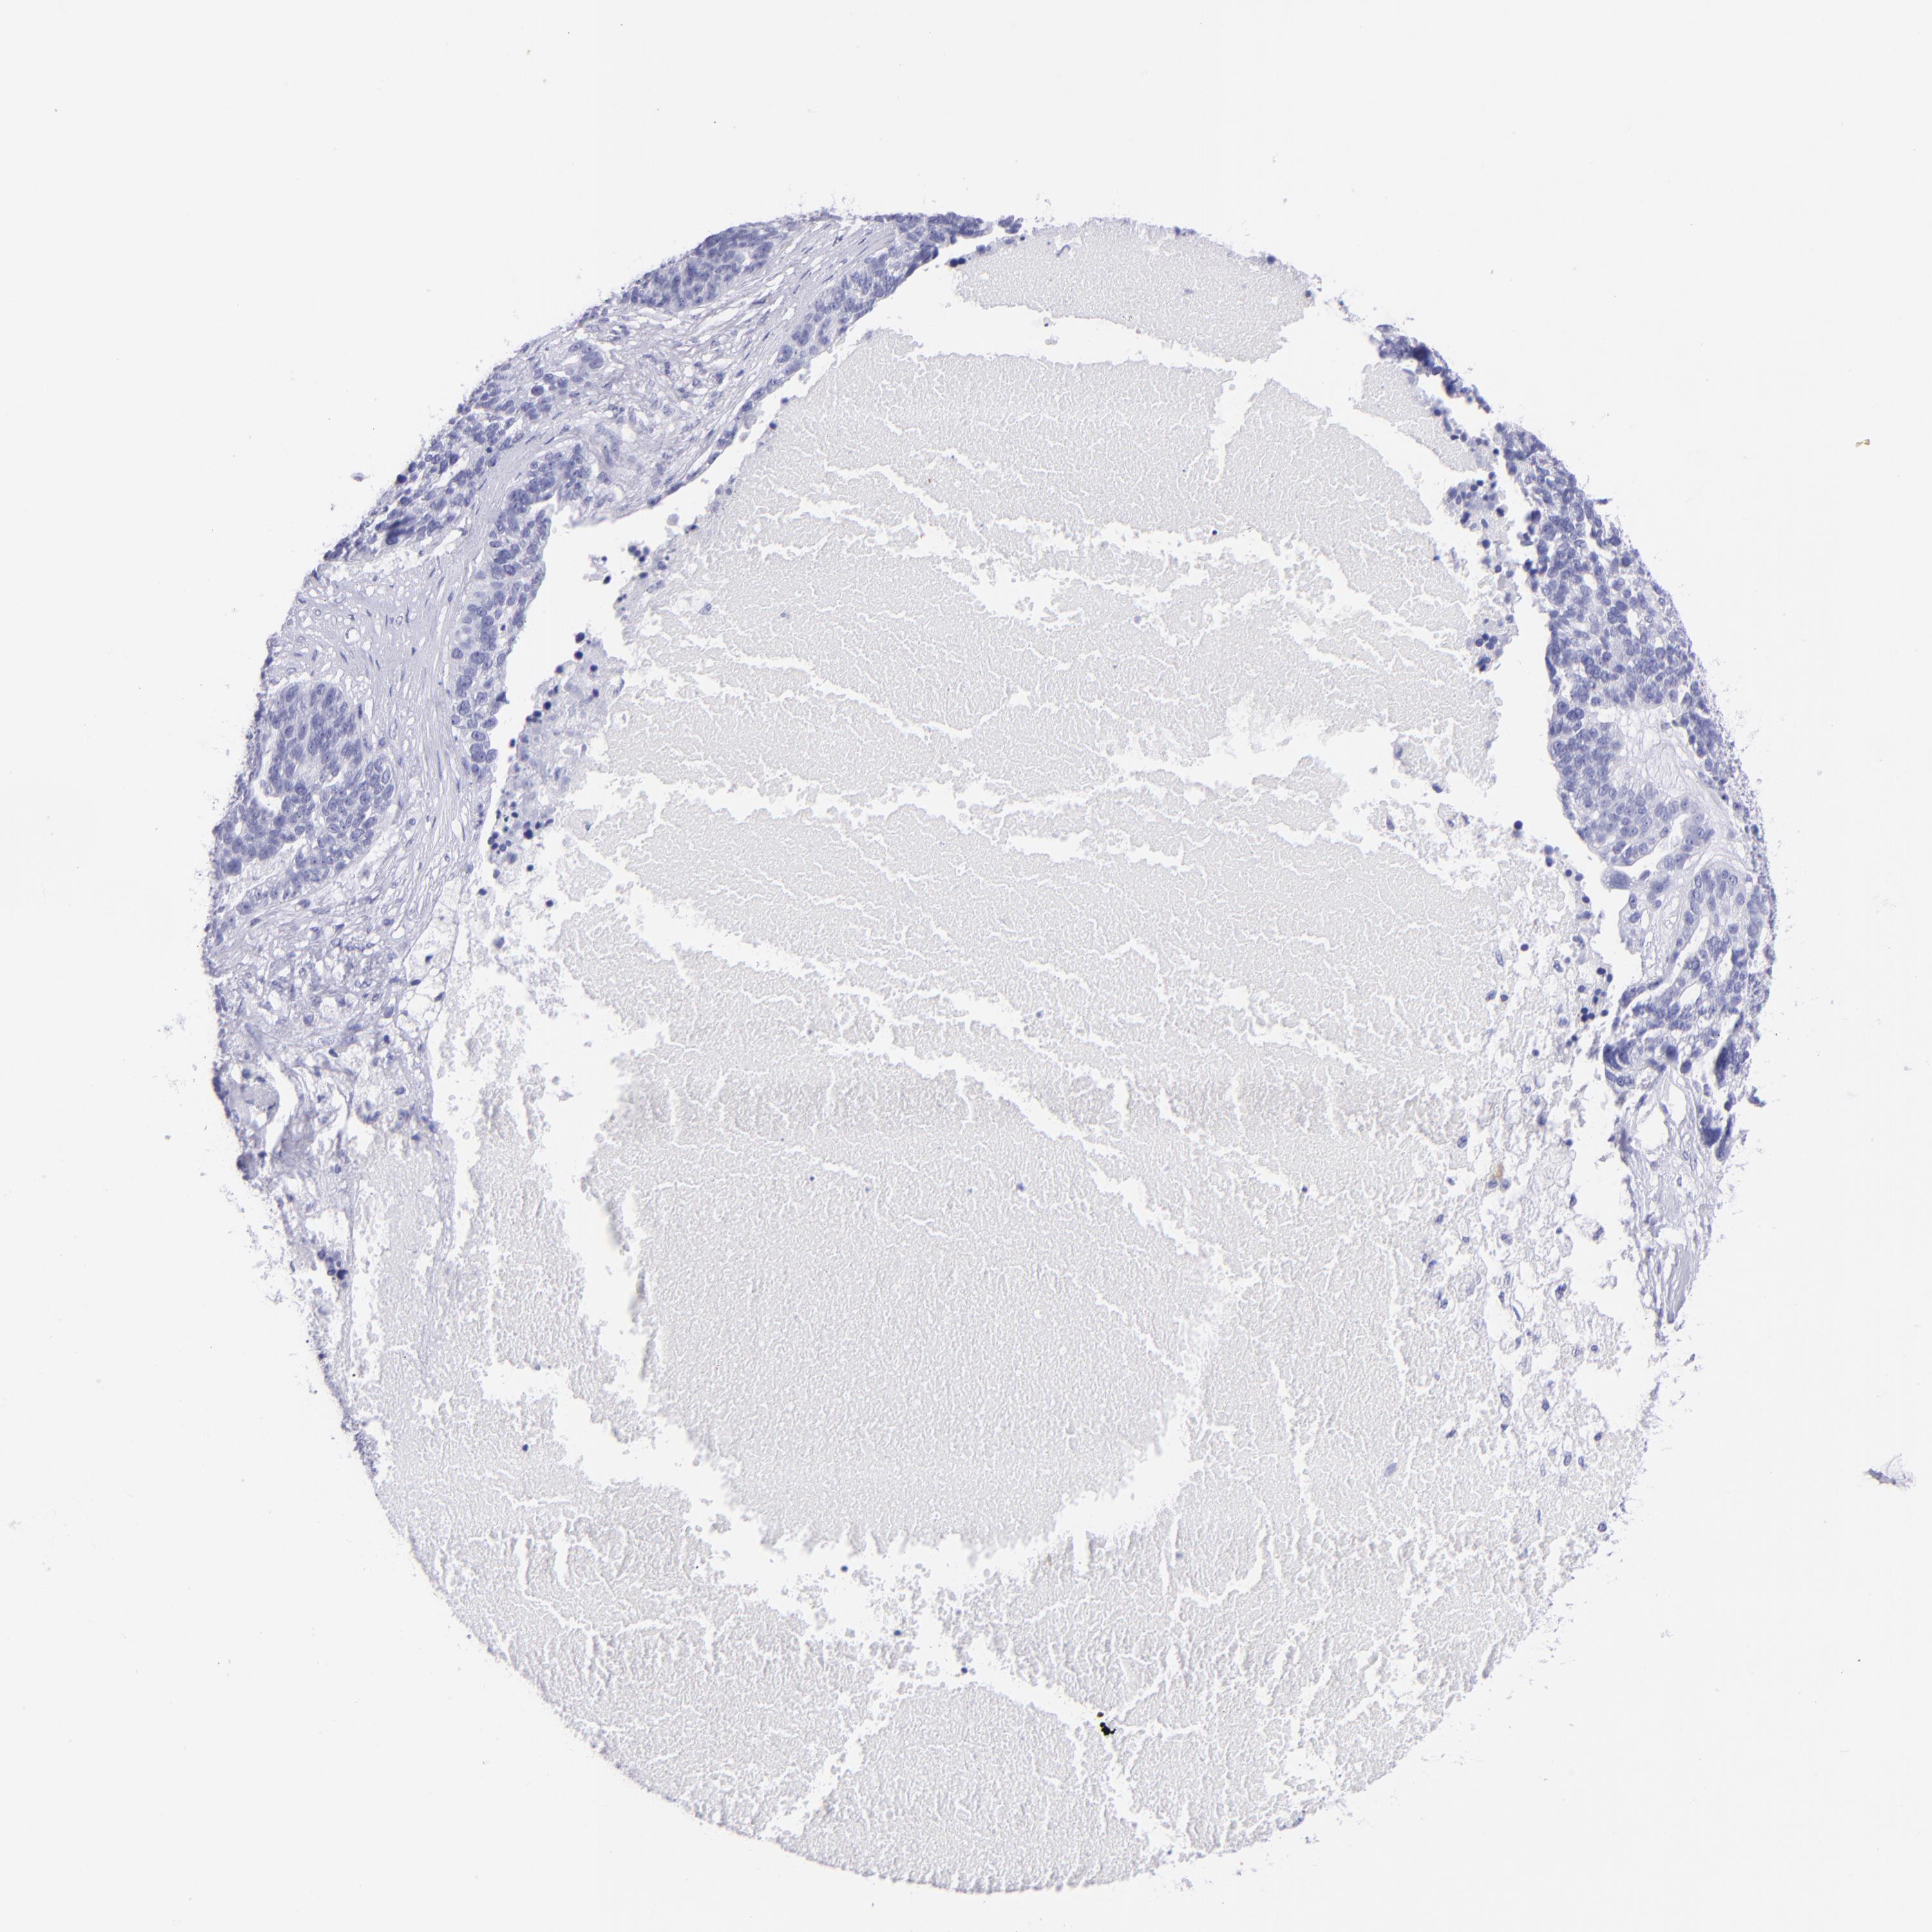

OVARIAN CANCER - Protein expressioni

A mouse-over function shows sample information and annotation data. Click on an image to view it in a full screen mode. Samples can be filtered based on level of antibody staining by selecting one or several of the following categories: high, medium, low and not detected. The assay and annotation is described here.

Note that samples used for immunohistochemistry by the Human Protein Atlas do not correspond to samples in the TCGA dataset.

Antibody stainingi

Antibody staining in the annotated cell types in the current human tissue is reported as not detected, low, medium, or high, based on conventional immunohistochemistry profiling in selected tissues. This score is based on the combination of the staining intensity and fraction of stained cells.

Each image is clickable and will lead to virtual microscopy that enables deeper exploration of all samples and also displays staining intensity scores, fraction scores and subcellular localization as well as patient and tissue information for each sample.

Antibody HPA009177

Antibody CAB002661

Staining

High

Medium

Low

Not detected

Intensity

Strong

Moderate

Weak

Negative

Quantity

>75%

75%-25%

<25%

None

Location

Nuclear

Cytoplasmic/membranous

Cytoplasmic/membranous,nuclear

Cystadenocarcinoma, serous, NOS

Carcinoma, endometroid

Cystadenocarcinoma, mucinous, NOS

Carcinoma, NOS